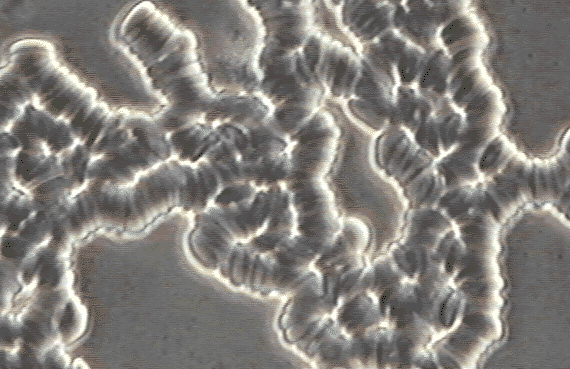

Do your red blood cells look like this? Mine did!

-W.S. 1/22/98

Before Microhydrin

Before

Microhydrin™

(See enlargement-96k)

Rouleau (clumped red blood cells) severely limits the access and availability of required nutrients and oxygen. An antioxidant may improve this.